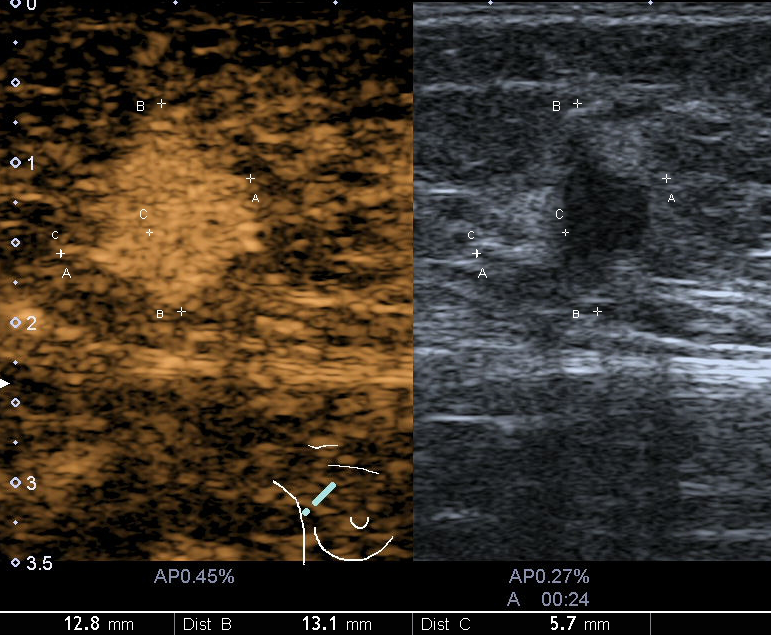

不打针,不开刀 超声造影鉴别甲状腺结节"良恶"

甲状腺行超声造影时的注意事项有哪些?